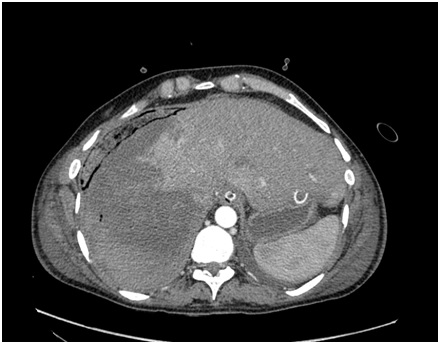

4. рис 2б | |

5. рис 3 | |